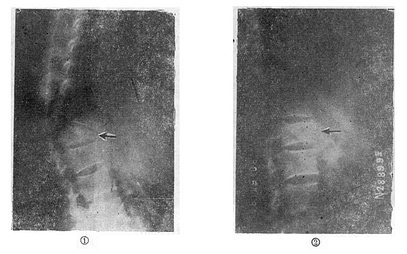

图73-12 垫枕背伸锻炼获良好结果 ①骨折初时;②背伸锻炼3个月后 (二)旋转型脊柱骨折的治疗 用Harrington棍法,不能矫正旋转,最好用Luque棍或Dick法进行矫正与固定。两根“L”型金属棍,放在棘突基底两侧,用每一个椎板下穿过的Luque钢丝固定到骨折部位上、下方各三个椎体椎板上,通过弯好弧度的Luque棍的杠杆作用和拧紧Luque钢丝所产生的矫正力,可以矫正旋畸形,并牢固固定骨折。如不合并神经系统症状,1周后即可下地活动。 (三)爆裂型骨折的治疗 如不合并严重的神经系统症状,损伤又在两周以内者,可以用双Harrington法,撑开矫正,或用Dick手术;可以获得满意的结果(图73-13)。复位后需融合相邻两个椎间隙,因为CT常显示在爆裂型骨折中,相邻的上、下两个椎间盘均有损伤,如不融合,日后取棍后会出现腰痛。使用本法时,如前纵韧带完整,则很容易恢复椎体前方的高度。但爆裂型骨折存在下述三种情况时,需行前路减压术:①合并神经系统症状较重者;②就诊较晚,已两周以上者(常常10天以上就复位比较困难);③脊柱CT扫描显示已有较大的骨折片突出椎管内,使髓腔管变窄超过30%以上者,预示后纵韧带已有明显损伤,使用后路手术方法已无法使骨折片复位。Kostuik复习了日本和多伦多治疗脊柱骨折的结果后证实,前路减压术能使膀胱、肛门及肢体功能得到更好的恢复。